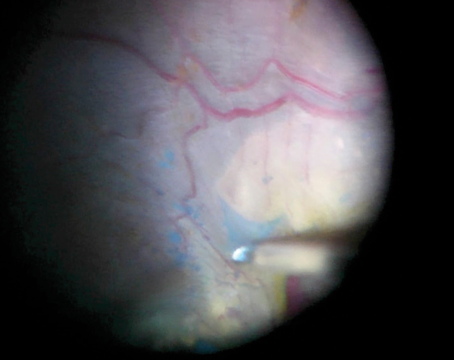

Pearls For Autologous Retinal Transplantation

An algorithm for successful graft sizing, harvesting and positioning in ART.

Retinal autograft with retinectomy and the SPOT technique for macular hole

The technique can be very useful in the setting of highly myopic PVR re-detachment.